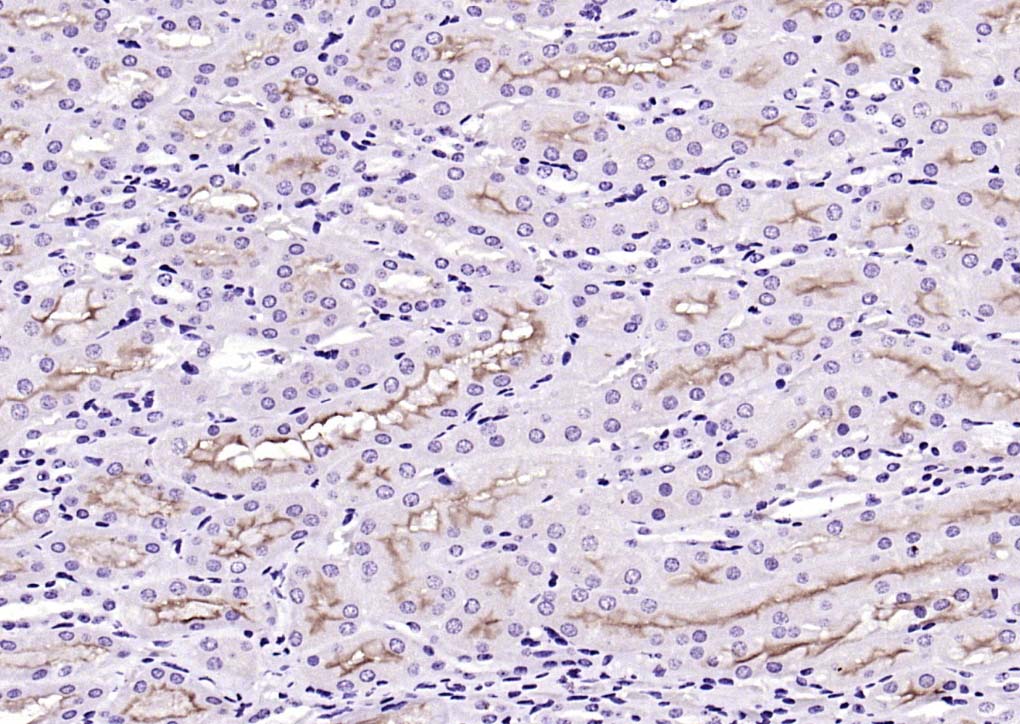

| IHC-P | Human, Mouse, Rat | 1:400-800 | |

| IHC-F | Human, Mouse, Rat | 1:400-800 | |

| IF | Human, Mouse, Rat | 1:100-500 |